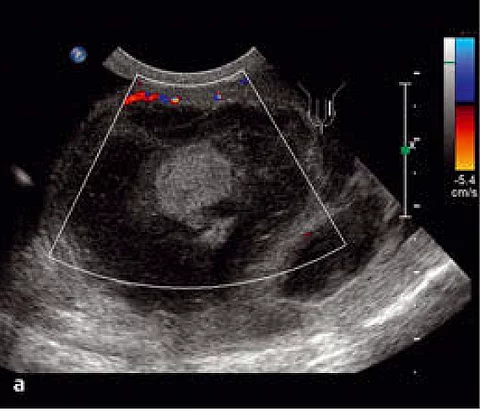

Seit einigen Wochen hatte die Patientin helles Blut im Stuhl. Bei der Prokto-Rektoskopie hatten Sie einen ulzerierten, blutenden Prozess gefunden. Die Histopathologie bestätigte den Verdacht.